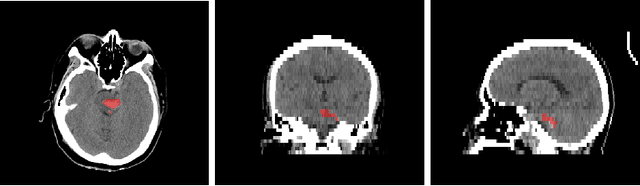

Intracranial hemorrhage segmentation challenge (INSTANCE 2022) offers a platform for researchers to compare their solutions to segmentation of hemorrhage stroke regions from 3D CTs. In this work, we describe our solution to INSTANCE 2022. We use a 2D segmentation network, SegResNet from MONAI, operating slice-wise without resampling. The final submission is an ensemble of 18 models. Our solution (team name NVAUTO) achieves the top place in terms of Dice metric (0.721), and overall rank 2. It is implemented with Auto3DSeg.